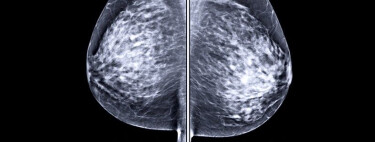

Scorul BI-RADS (un acronim pentru Breast Imaging Reporting and Database System, sistemul de baze de date și raportare în imagistica sânului) este un scor de risc utilizat de medicii radiologi pentru a descrie rezultatele mamografiei sau ale unei ecografii mamare.

Colegiul American de Radiologie a impus scorul BI-RADS ca sistem de interpretare și raportare a aspectelor constatate de imagistica mamară, din care decurge o anumită strategie. Acesta a fost inițial utilizat pentru aspectele mamografice, dar indiscutabila sa valoare l-a impus și pentru cele ecografice sau de la imagistica prin rezonanță magnetică (RMN), în cazul unui RMN mamar. Modul exemplar prin care scorul BI-RADS clarifică informația imagistică a determinat acceptarea unanimă și universală a acestuia de către toate categoriile de specialiști ce activează în domeniul senologiei (medici imagiști, chirurgi, oncologi, anatomopatologi etc.).

Examenele imagistice se efectuează în scopul depistării (în programe naționale sau oportunist) sau diagnosticării (ocazionat de autodepistarea de noduli sau apariția de simptome) cancerului de sân. Depistarea se efectuează în condiții ce scuză neclaritățile (urmează a fi elucidate într-o secvență diagnostică), în timp ce diagnosticul angajează foarte serios responsabilitatea examinatorului de a da o rezoluție cazului.

Circumstanțele au importanța lor: rezultatul este judecat în concordanță cu riscul evaluat pentru pacienta în cauză și (preferabil) dispunând de rezultate imagistice anterioare. Fondul imagistic poate presupune el însuși neclarități: densitatea mamară crescută, cicatricele după operații mamare sau situația premenstruală pot ascunde mamografic unele leziuni. La fel pot face neomogenitatea extremă sau mărimea exagerată a sânilor, în cazul ecografiei mamare.

Densitatea mamară

Colegiul American de Radiologie a clasificat densitatea mamară crescător, de la A la D. Astfel, C poate ascunde mici leziuni, iar D poate ascunde orice leziune.